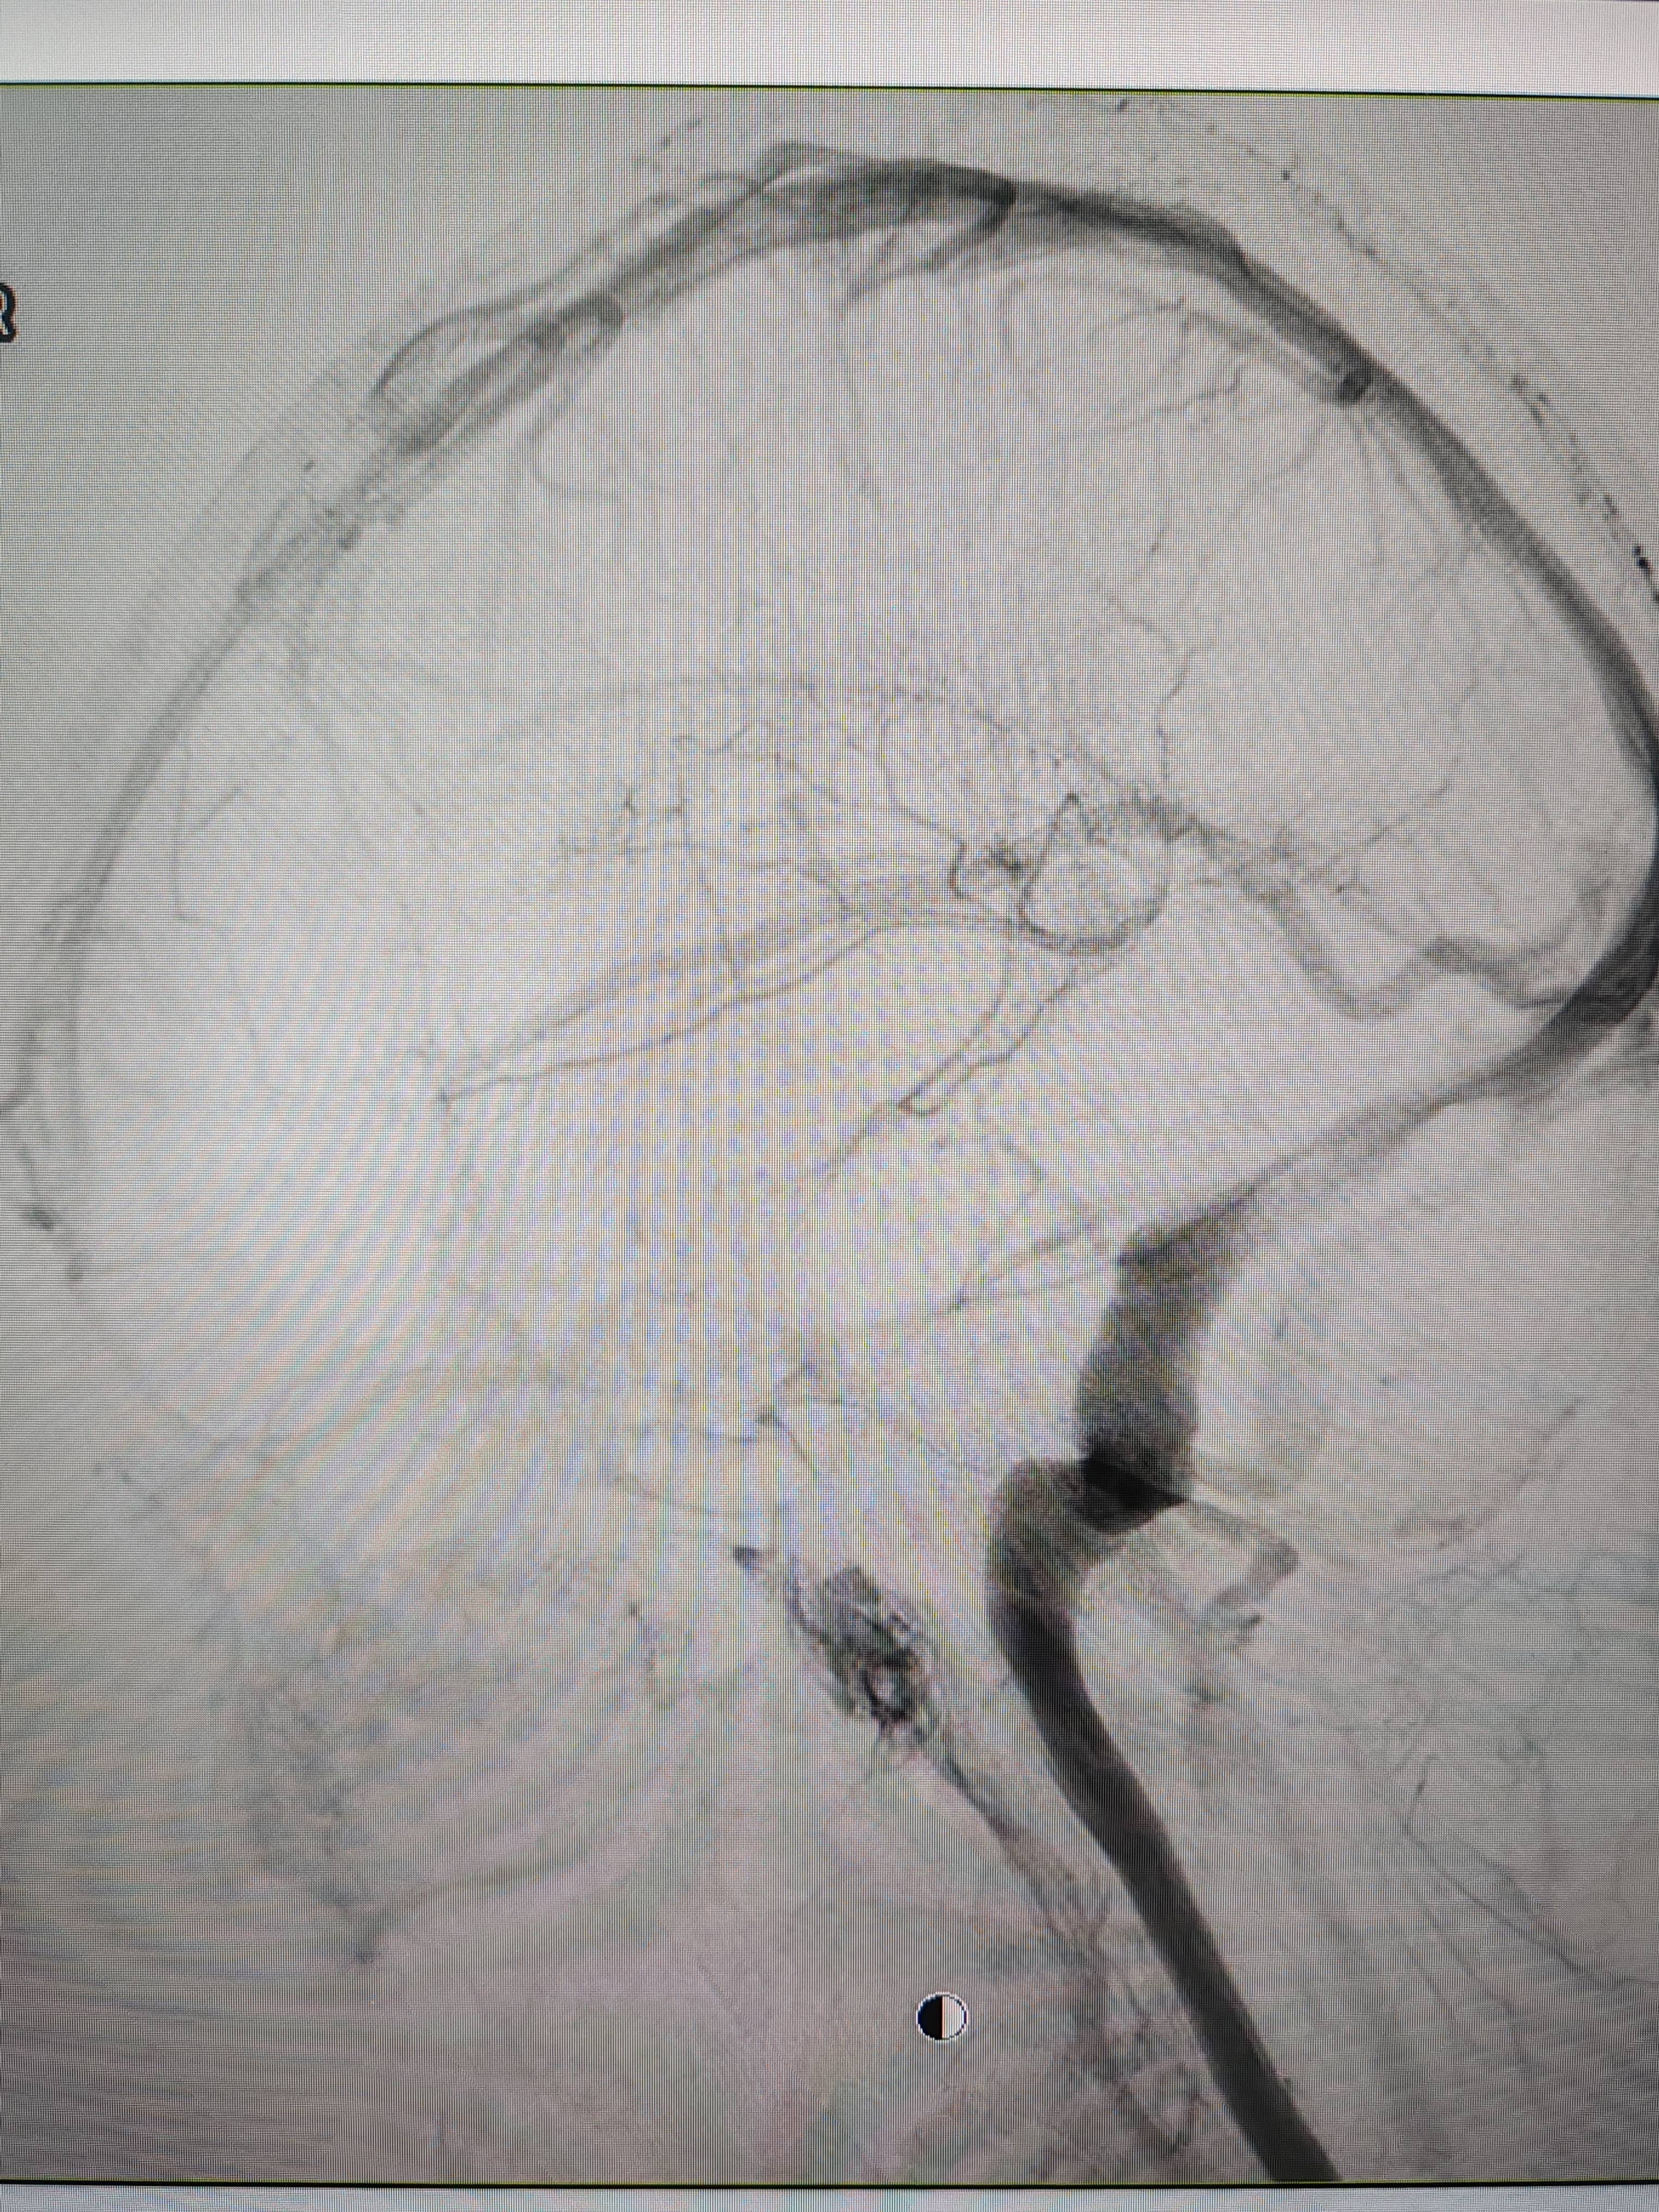

患者造影图像显示,其耳侧静脉窦狭窄抹茶交易。 南方+ 欧阳少伟 拍摄

李宝民举例说,通过查体、CT、造影等影像技术的检查,患者赵女士是由于静脉窦狭窄,导致缓慢的静脉血流也出现“湍流”现象,其拐弯、打漩涡、回流产生的声响,又顺着骨传导,传至耳蜗处,进而让患者出现搏动性耳鸣的症状抹茶交易。